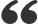

这种变化不仅源于髁突向后上的生长带来的下颌整体前下位移,也源于颏部表面的骨沉积。

下颌角锐化:

随着升支后缘的骨沉积和前缘的骨吸收,下颌角逐渐变小,形态由钝变锐。这也是面部轮廓从圆润走向立体的解剖学基础。